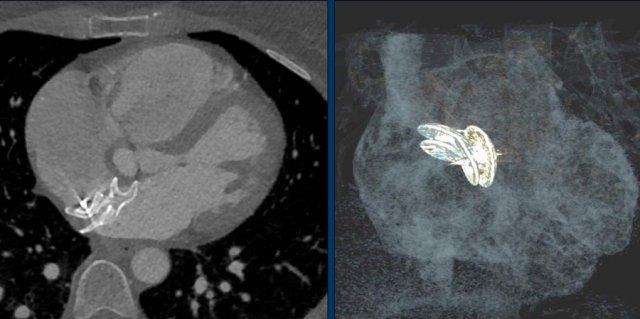

Các phát hiện bao gồm:

- Hai điện cực thượng tâm mạc kết nối với máy tạo nhịp

- ICD

- Hai điện cực đến mỏm thất phải

- Một điện cực chứa hai cuộn sốc điện

- Van ba lá (mũi tên)

- Van hai lá